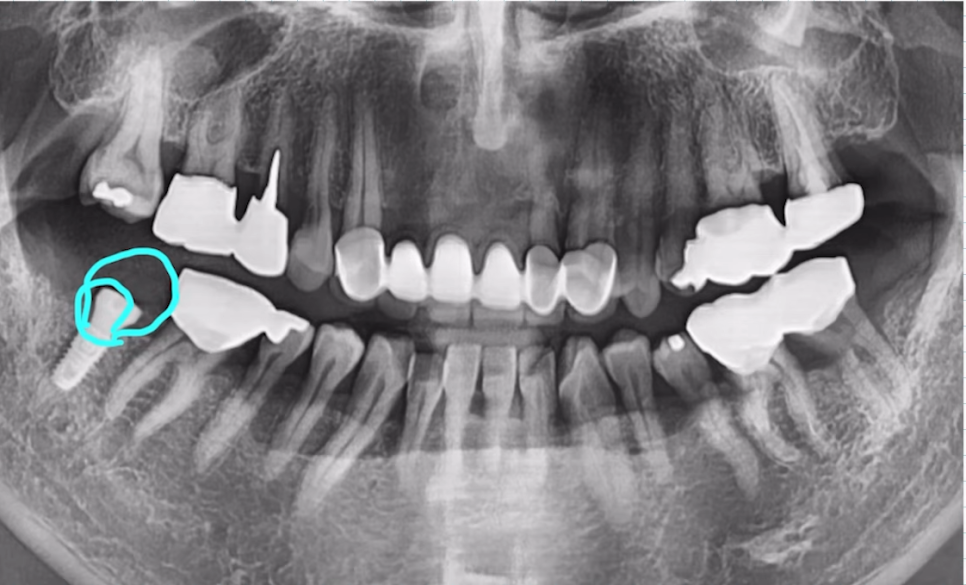

"오른쪽 아래 어금니가 아파요" 하고 오신 환자분이신데요.

CT 촬영 결과 안쪽 뼈는 양호했지만, 바깥쪽 뼈는 매우 얇은 상태였습니다.

이 경우 무리하게 당일임플란트를 진행하면 뼈 흡수나 식립 실패 가능성이 크죠.

그래서 저는 발치 후 즉시 심지만 안쪽으로 깊게 심어드렸습니다.

안쪽 뼈는 외측보다 뼈 흡수가 덜 되고, 밀도도 더 높은 경우가 많기 때문에

임플란트를 안쪽으로 깊게 심어 고정력을 더 확보했습니다.

임플란트 식립 이후 뼈도 잘 차오르고, 예후도 좋은 모습을 볼 수 있습니다.